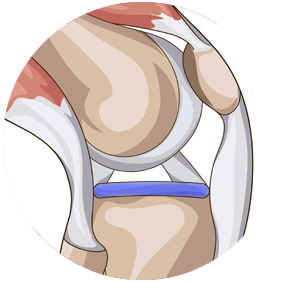

Prothèse totale

du genou

Quand l'usure des cartilages devient significative (arthrose), accompagnée de douleurs importantes et que cela entraîne une perte de mobilité sérieuse, la solution proposée est une prothèse totale de genou.